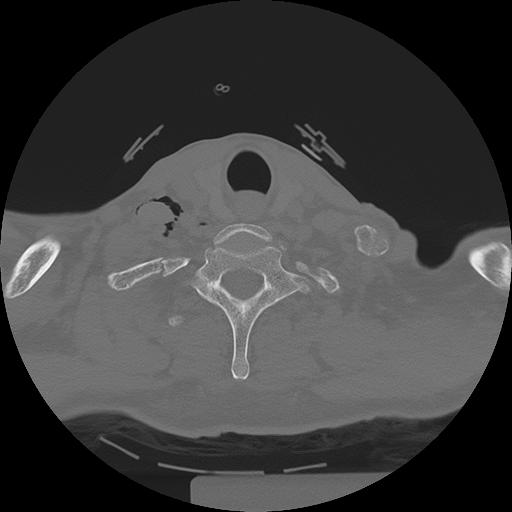

11 HUESO,,Axial,2.0,HUESO,,